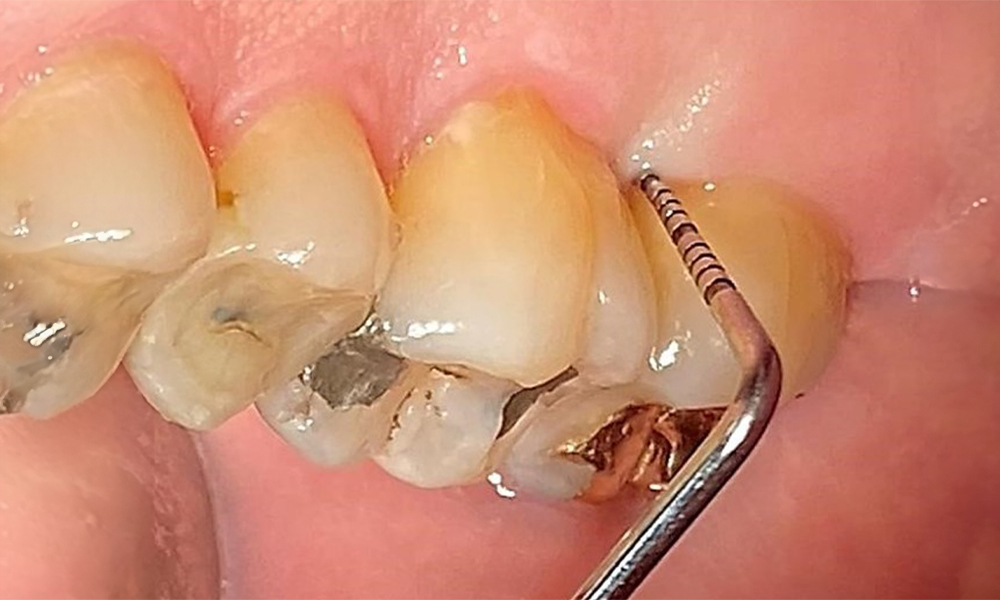

Probing to document the findings in tooth 27 mesiopalatal. © Dr R. Krapf

Fig. 8: Probing to document the findings in tooth 27 mesiopalatal. © Dr R. Krapf

The documentation of periodontal findings, including pocket depth probing and bleeding status, is mandatory during each dental appointment due to the presence of periodontitis (Fig. 8). This will record the individual therapeutic needs and facilitate a rapid response to any progression of the pre-existing periodontitis.